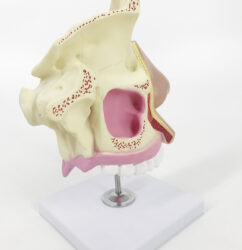

ATL-114 ADVANCED EAR INPECTION SIMULATOR SOFT

ATL-115 ADVANCED EAR IRRIGATION SIMULATOR SOFT

ATL-116 ADVANCED EAR DIAGONOSTIC SIMULATOR SOFT